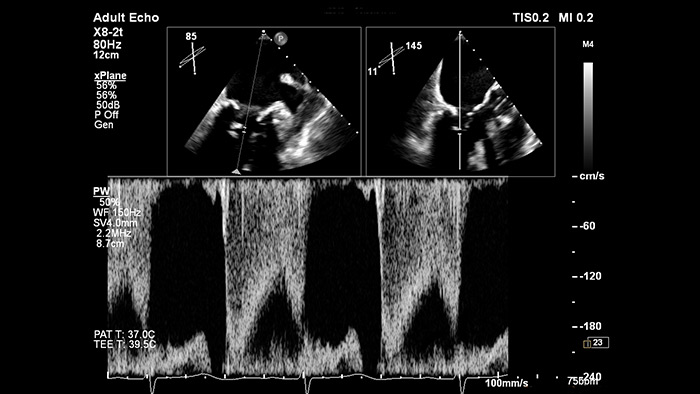

Gain confidence of correct gate placement when assessing cardiac flow with xPlane Doppler